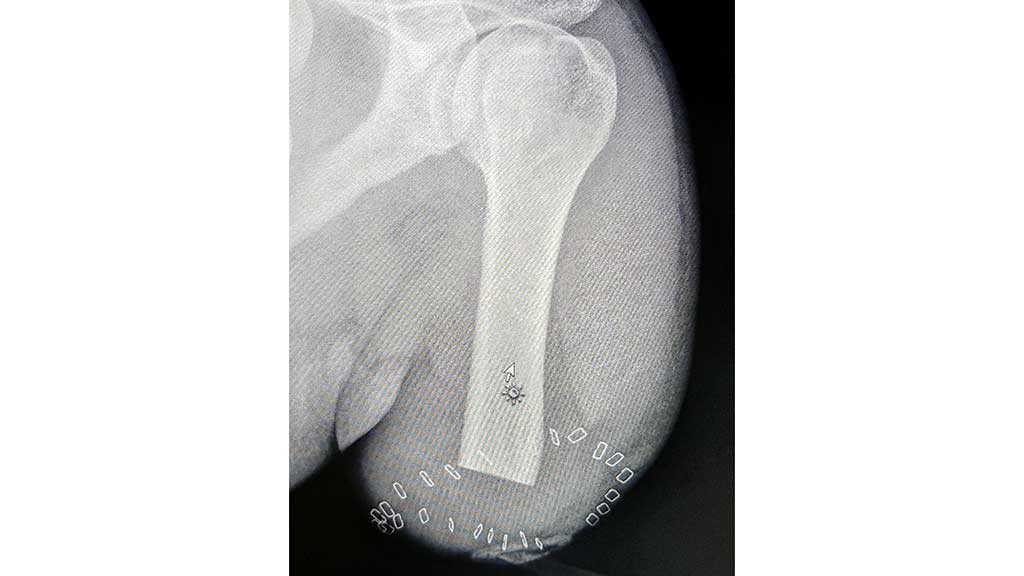

Schon in der Erstberatung des Patienten bezüglich seiner Versorgung, die vom Autor durchgeführt wurde, stand fest, dass der verunfallte Patient einen hohen Anspruch an seine Lebensqualität nach der Amputation und damit an die Prothesenversorgung stellen würde. Denn neben der Rückkehr in sein Familien- und Berufsleben wollte er auch seinen Sport wieder aktiv betreiben können. Aufgrund der Amputationshöhe mit kurzem Oberarmstumpf (Amputation im Bereich des proximalen Drittels des Oberarms) 7 (Abb. 3) und seines klar definierten hohen Anspruchs an eine spätere Versorgung wurde für den 24.08.2020 eine Beratung bezüglich einer TMR-OP inklusive einer Osseointegration an der Universitätsmedizin Göttingen terminiert.

Für diese Variante muss unter anderem das Skelett des Patienten ausgewachsen sein; zudem ist eine Humerus-Mindestlänge von 8 cm notwendig. Beim hier vorgestellten Patienten war diese Vorgabe gegeben; seine Humeruslänge entspricht genau dieser vorgegebenen Mindestlänge. Ziel war es, eine hochfunktionale Prothese und eine entsprechende Prothesenansteuerung zu erreichen, gepaart mit einer einfachen Handhabung für den Anwender in seinem Alltag.